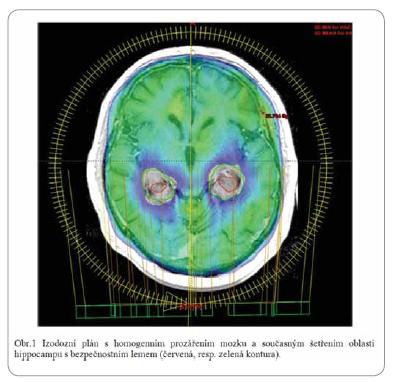

Moderní systémy radioterapie umožňují adekvátní ozáření cílového objemu se současným šetřením prakticky jakkoliv tvarované a orientované struktury kritických orgánů, např. oblasti hippocampu (obr. 1). Právě v této části mozku, v subgranulární vrstvě gyrus dentatus, se vyskytují neuronální kmenové buňky, které se podílejí na neurofyziologických procesech spojených s pamětí. Z radiobio logického hlediska jsou tyto buňky citlivé k nízkým dávkám ionizujícího záření, což může vést k alteraci paměti a dalších kognitivních funkcí. Existují teoretické předpoklady podporující ověření konceptu radioprotekce hippocampu v klinické praxi. V ústním sdělení budou představeny dvě probíhající studie fáze II testující závislost výskytu poruch paměti a ozáření oblasti hippocampu. U pacientů v experimentálním rameni je cíleně chráněna oblast hippocampu se současným ozářením ostatní mozkové tkáně standardní dávkou (ve druhé studii navíc s boostem na oblast metastáz). Rovněž v radioterapii primárních mozkových tumorů lze optimalizovat ozařovací plány ve smyslu radioprotekce hippocampu (low grade gliomy, meningeomy).